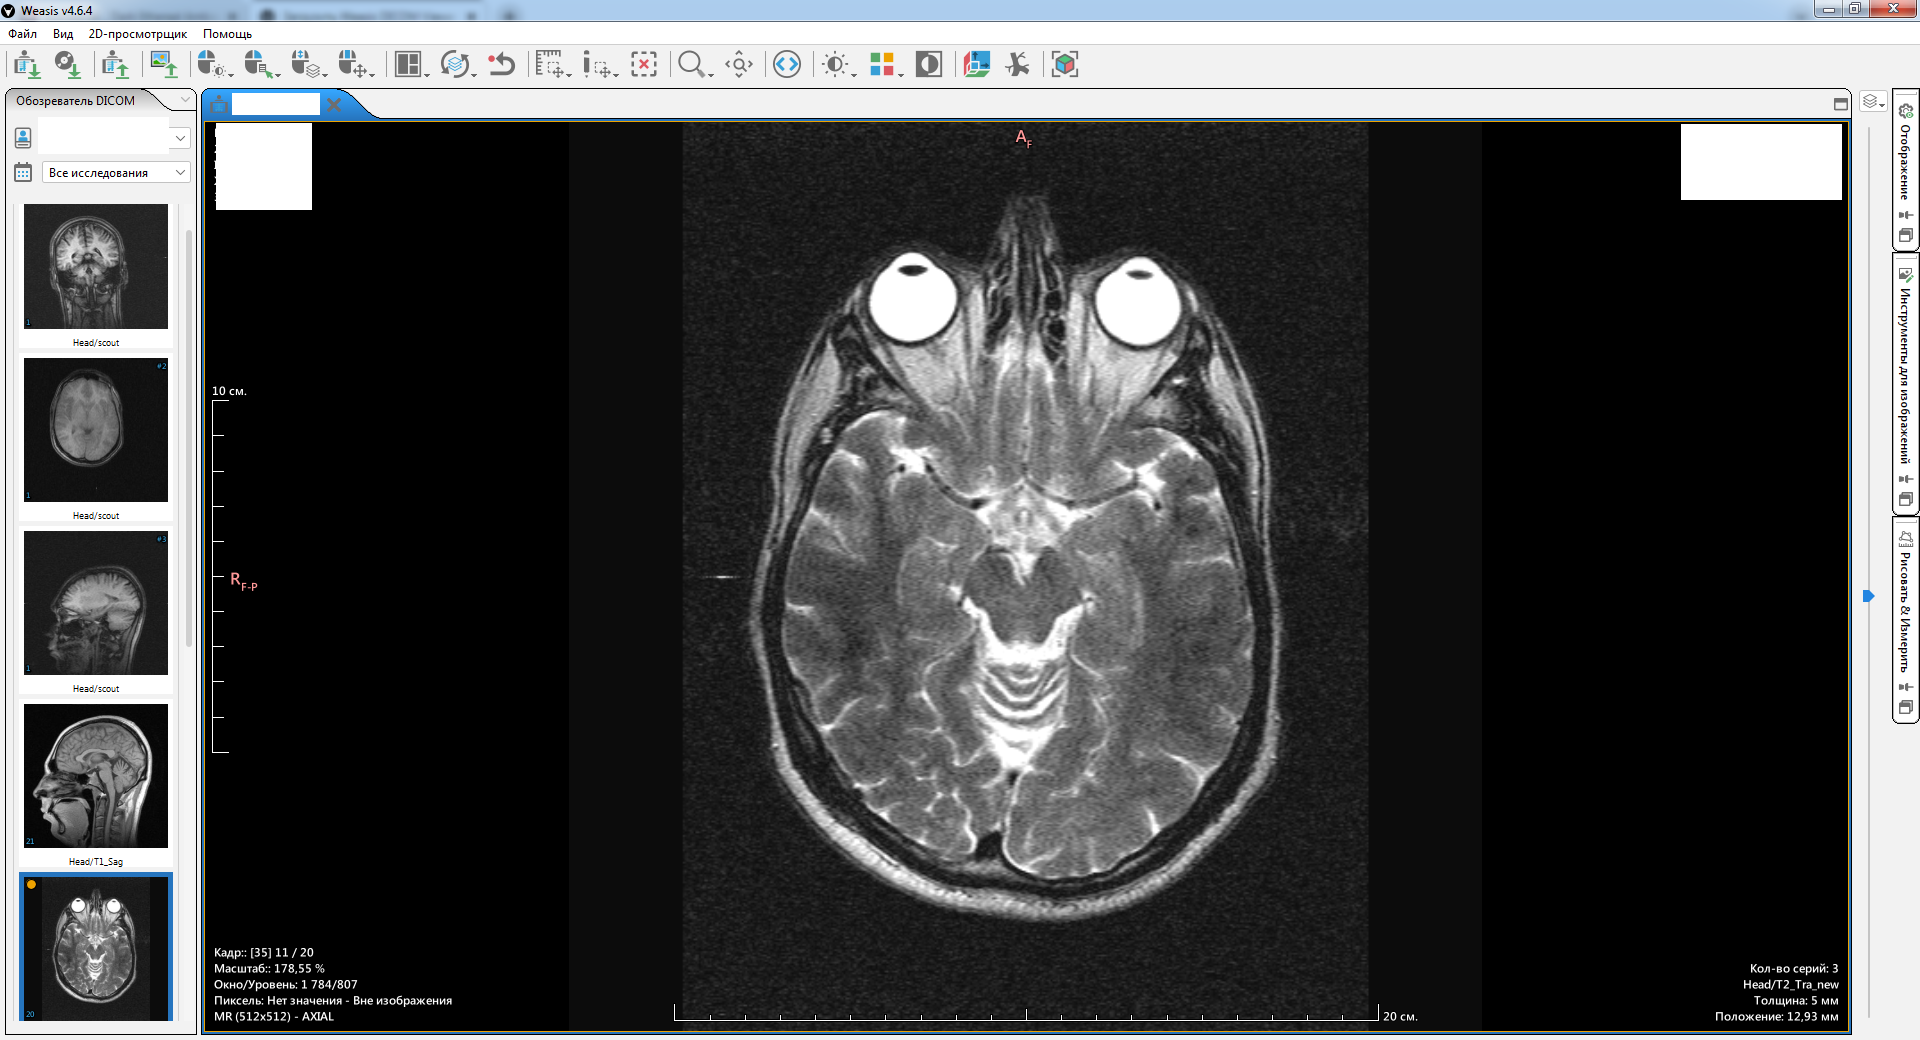

Будь мы врачами или пациентами, которым не всё равно на своё здоровье — нам нужна своя полноценная читалка. Их много, большая часть коммерческая, но существует несколько бесплатных альтернатив очень приличного качества. Одной из них является Weasis:

Сайт с документацией, скачать под разные системы можно тут.

С тавим, радуемся, пользуемся.